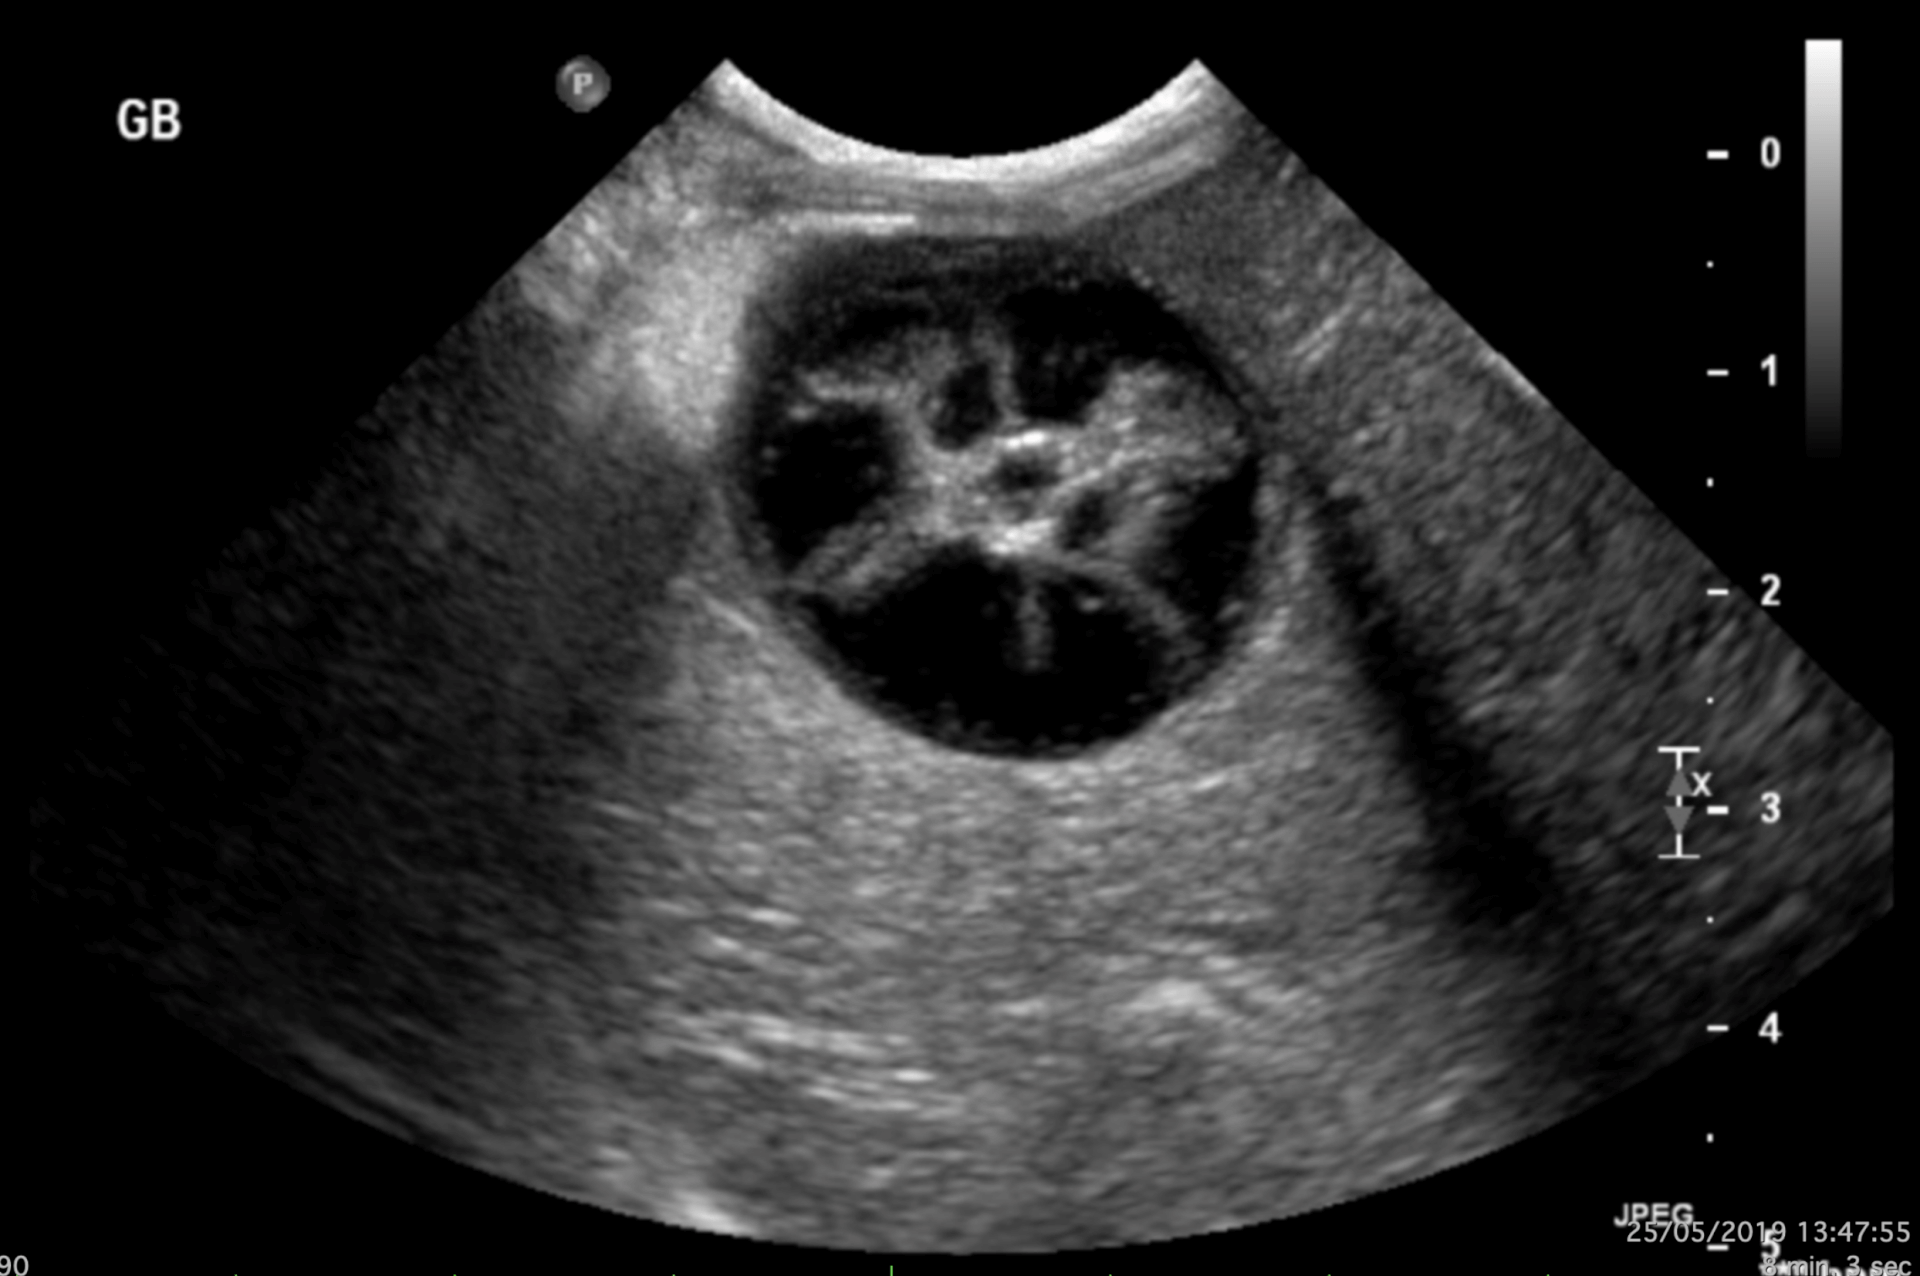

Mucocoele biliaire (@Emilie Fauchon)

Le diagnostic repose sur l’imagerie médicale, principalement l’échographie. Les caractéristiques typiques incluent :

- Une apparence striée ou étoilée (semblable à un kiwi).

- Une épaississement de la paroi de la vésicule biliaire.